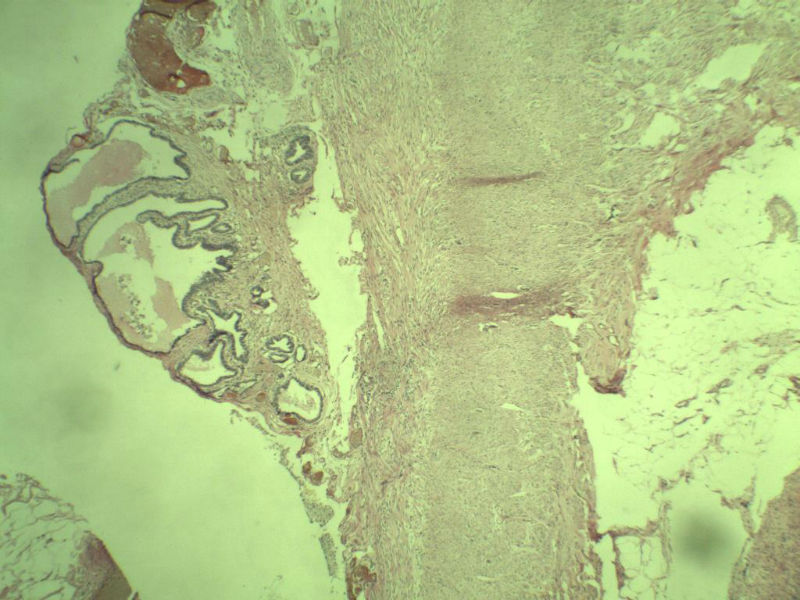

女性患者,42岁 阑尾 大体上看没问题 但是这些东西是什么?? 请指教,谢谢了!